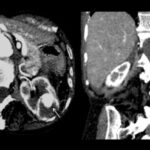

Resultados según clasificación Bosniak

- Bosniak I: el 80% de los quistes (418 pacientes) fueron clasificados como Bosniak I, es decir, quistes simples hallados incidentalmente en tomografía computada (TC) y sin necesidad de seguimiento adicional. De estos, 268 pacientes eran de sexo masculino y 150 de sexo femenino (Anexos 17 y 18).

- Bosniak II: el 10% de los quistes (55 pacientes) fueron catalogados como Bosniak II, correspondientes a quistes benignos. Esta categoría incluyó a 36 pacientes de sexo masculino y 19 de sexo femenino (Anexos 19 y 20).

- Bosniak IIF: en esta categoría, el 4% de los quistes (20 pacientes) presentaron complicaciones. De estos, el 70% (14 pacientes) presentaron quistes hemorrágicos, mientras que los restantes presentaron calcificaciones parietales. En un caso (2% de esta categoría) se observó evolución hacia malignidad, con realce en la TC (Anexo 21).

- Bosniak III: el 3% de los quistes (15 pacientes) fueron clasificados como Bosniak III, con 11 pacientes de sexo masculino y 4 de sexo femenino (Anexo 22).

- Bosniak IV: finalmente, el 3% de los quistes (15 pacientes) fueron clasificados como Bosniak IV, de los cuales 12 pacientes eran de sexo masculino y 3 de sexo femenino. Estos quistes presentaron características de neoplasia quística renal y carcinoma renal quístico, lo que requirió intervención quirúrgica inmediata (Anexo 23).